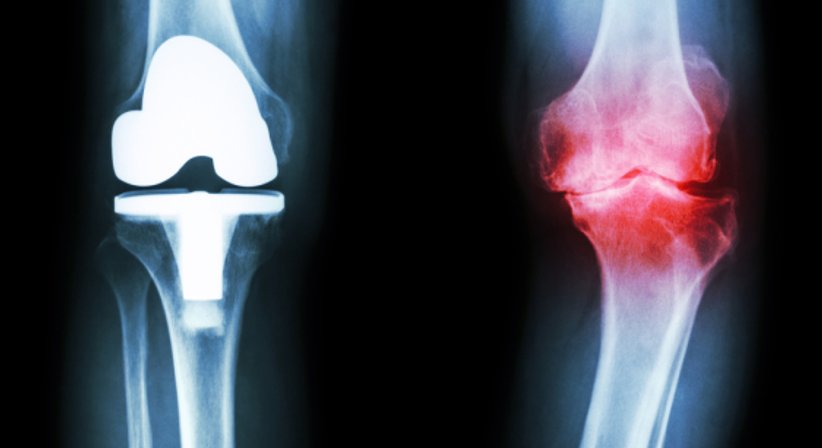

Arthrose im Kniegelenk (Gonarthrose) führt bei Betroffenen mit der Zeit zu starken Schmerzen und massiven Bewegungseinschränkungen. Die Gelenkerkrankung ist durch einen Abbau des Gelenkknorpels charakterisiert und kann vor allem zu Beginn gut mithilfe konservativer Maßnahmen (z.B. Physiotherapie, physikalische Therapie, medikamentöse Therapien, Infiltrationen) behandelt werden. Allerdings ist Arthrose nicht heilbar - der Abbau vom Gelenkknorpel kann nicht wieder rückgängig gemacht werden.

Bei Knieprothesen handelt es sich um implantierte Prothesen (Endoprothesen), die das Kniegelenk ganz oder teilweise ersetzen. Letztere Variante (Schlittenprothese) kommt dann in Frage, wenn nur ein bestimmter Teil vom Kniegelenk von Abnutzung betroffen ist, während die Bänder im Knie noch gänzlich erhalten und funktionsfähig sind.

Die Aufgabe einer Knieprothese ist es, die Form und die Funktion des Kniegelenks nachzuahmen. Für die Implantation stehen unterschiedliche Knieprothesen zur Wahl. Da jedes Knie anders ist und jeder Patient individuelle Bedürfnisse und Ansprüche hat, setze ich bei der Implantation einer Knieprothese auf ein Modell, welches im Rahmen der Behandlung exakt an die individuelle Anatomie des Patienten angepasst wird.